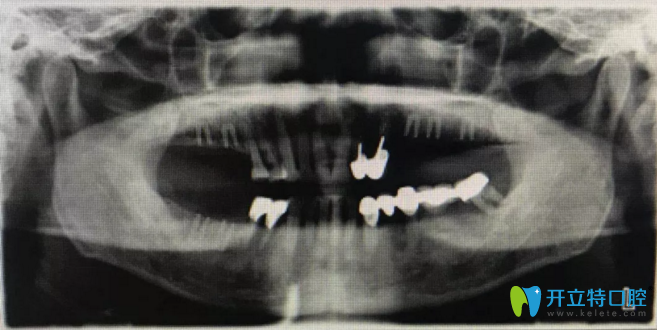

種植后全景片